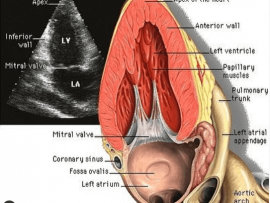

Lee masApical 2 chamber view Importance: 1)Assessment of Ischemia “RWMAs” 2)Viewing LV apical thrombus 3)Assessment of MR and its mechanism 4)Assessment of pericardial effusion 5)viewing Coronary sinus and LAA ..